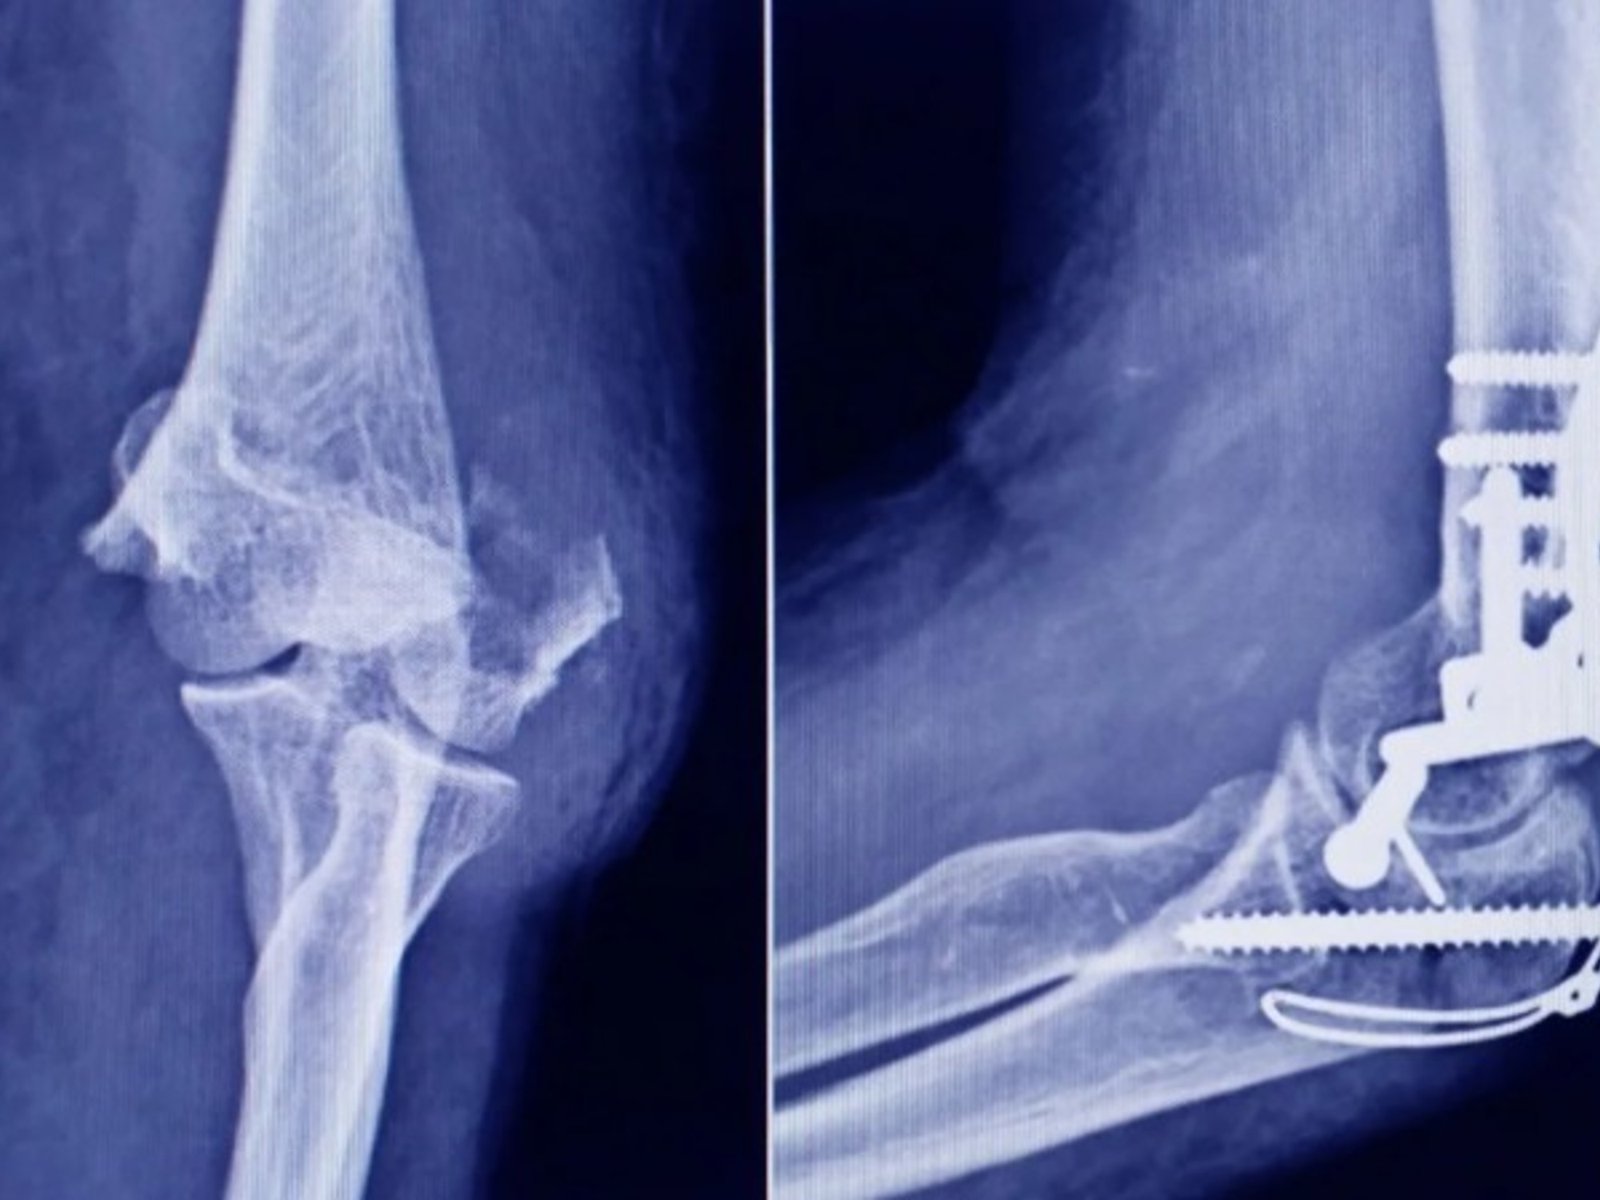

La Administración Nacional de Medicamentos, Alimentos y Tecnología Médica (ANMAT) advirtió a la población por un tornillo que se utiliza en cirugías traumatológicas y es falso, lo que representa riesgo para la salud del paciente al que se lo implante. Fue detectado durante una inspección de control de mercado realizada en una ortopedia ubicada en la ciudad de San Miguel de Tucumán.

El tornillo, utilizado en cirugías traumatológicas, tiene una medida de 10 mm x 28 mm y entre las diferencias halladas entre un producto original y falso se encontró que el de la empresa Stryker tiene fecha de fin de vigencia, mientras que la unidad falsificada no cuenta con ese dato.